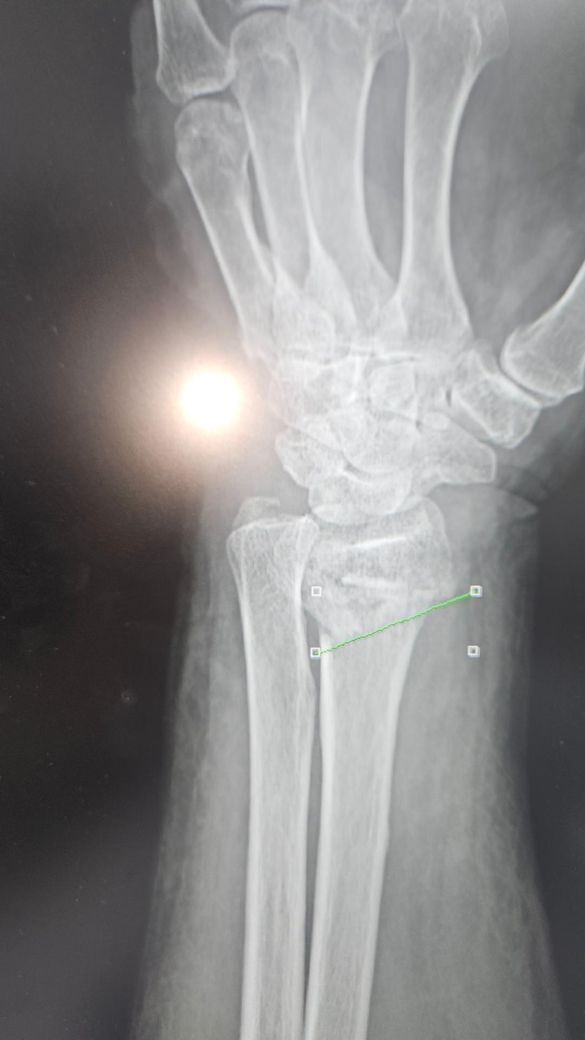

• 3번 째 사진

엑스레이상 골절부위의 어긋남이 심한편이라 병원에서 수술을 권한걸로 보입니다. 현재사용중인 탈부착형 보조기는 세척과 치료는 용이하나 86세 고령환자의 불안정한 골절을 고정하기엔 힘이 부족할수 있습니다. 처방된 약은 단순 진통제가 아니라염증과 붓기완화 목적도 있으므로 임의 중단은 피하는게 좋습니다.현재치료비용과 고정의 불확실성을 고려할때 수술이 정 어렵다면 통깁스를 통해 아예 움직임을 제한할수 있게 고정하는 방안을 담당의사와 상의하는걸 추천드립니다. 뼈가 붙지 않은 상태에서 한의원 방문보다 정형외과적 고정이 최우선입니다. 빠른쾌유를 빕니다.

엑스레이상 손목 요골 원위부 골절로 보이며, 고령에서는 정복이 유지되지 않아 변형 유합 위험이 있습니다.

반깁스를 자주 풀고 다시 고정하면 실제로 정렬이 틀어질 수 있어, 안정적 고정(깁스 유지)이 더 중요합니다.

제시된 X-ray와 경과를 종합하면 관절면을 일부 포함한 원위 요골 골절에 전위가 있었고, 정복 후에도 고정이 안정적으로 유지되지 않는 흐름입니다. 특히 반깁스를 반복하면서 정렬이 흔들린다는 점은 비수술 치료의 핵심 조건인 “정복 유지”가 실패할 위험 신호입니다. 이런 경우 시간이 지나면 부정유합으로 이어지고, 손목 변형과 회전 제한, 악력 저하가 남을 가능성이 높습니다.

지금 제시된 영상은 전형적인 원위 요골 골절로 보이며, 관절면을 일부 침범하면서 전위가 동반된 형태 가능성이 있습니다. 고령에서 흔한 골다공증성 골절 양상과 일치합니다. 정복 후 유지가 핵심인데, 현재 사진과 경과 설명상 “정복 유지 안정성”이 충분한지 의문이 있습니다.

비수술 치료의 적응은 [전위가 크지 않고, 정복 후에도 정렬이 유지되는 경우]입니다. 반면 다음 상황이면 수술을 고려하는 것이 일반적입니다. 관절면이 어긋난 경우, 등쪽으로 많이 꺾인 경우, 요골 길이 단축이 있는 경우, 그리고 정복 후에도 다시 틀어지는 경우입니다. 현재처럼 반깁스를 자주 풀고 다시 고정하면서 정렬이 반복적으로 변한다면, 유지 실패 가능성이 높습니다.

86세 고령, 뇌졸중 병력, 당뇨, 고혈압이 있는 점은 수술 위험을 분명히 증가시키지만, 최근 가이드라인에서는 “기능 요구도가 낮고 변형을 어느 정도 감수 가능”하면 비수술도 허용됩니다. 다만 이 경우에도 최소한 초기 1주에서 2주 동안은 정복 상태가 유지되는지 연속적인 X-ray 확인이 중요합니다. 3주차인데 붓기 변동과 함께 정렬 유지가 불안정하다면, 이미 부정유합 방향으로 진행 중일 가능성도 배제할 수 없습니다.

현재 치료 방식에 대해 말씀드리면, 골절 초기 2에서 3주는 부종 변화가 커서 고정이 느슨해질 수 있습니다. 그래서 보통은 “완전 석고 고정” 또는 잘 맞춘 보조기 형태로 유지하고, 불필요하게 자주 풀지 않는 것이 원칙입니다. 매번 다른 사람이 반깁스를 감고 정렬이 달라지는 상황은 표준적이라고 보기는 어렵습니다. 특히 관절면 골절에서는 정밀한 고정 유지가 중요합니다.

치료 방향은 다음과 같이 정리됩니다. 첫째, 현재 정렬 상태를 다시 정확히 평가해야 합니다. 최근 X-ray에서 각도, 길이, 관절면 상태를 확인해야 합니다. 둘째, 정렬이 이미 많이 틀어졌다면 지금이라도 수술 또는 기능적 결과를 감수하는 보존치료 중 하나를 명확히 선택해야 합니다. 셋째, 비수술 유지 시에는 고정 방법을 단순화하고 안정적으로 유지해야 합니다. 잦은 재고정은 오히려 불리합니다.